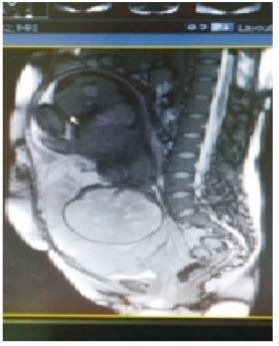

MRI检查提示:胎盘附着于子宫中下段前后下壁,完全覆盖宫颈内口,子宫胎盘母面见血管怒张,见增粗迂曲明

显扩张血管,见图2。

图2盆腔MRI矢状面截图